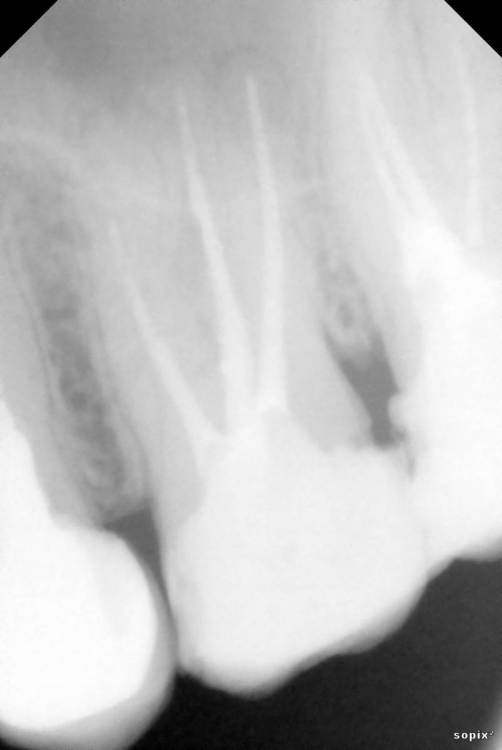

Siegfrid Опубликовано 29 июля, 2021 Поделиться Опубликовано 29 июля, 2021 Был у нескольких врачей в разных клиниках и мнения разошлись. В двух клиниках нашли проблемы сумма оказалась большой сходил в недорогую клинику, там проблемы не видят.. 2.6 и 2.7 Зуб со свищем 2 разных врача берутся лечить с шансом примерно 40% на успех, 1 врач говорит что только удаление. Ссылка на комментарий

Siegfrid Опубликовано 30 июля, 2021 Автор Поделиться Опубликовано 30 июля, 2021 Между зубами 2.6 и 2.7 набивается еда и гниет, когда я пошел в клинику на консультацию когда сделали снимок нашли что также плохо полечены каналы и для полного лечения двух зубов оказалась большая сумма которой у меня нету, я об этом сказал тогда мне предложили перепломбировать чтобы не набивалась еда, предупредив что непролеченные каналы со временем приведут к потере зубов. Я сходил в другую клинику, врач нашел кариес на одном из этих зубов но так как уходил в отпуск записал к другому врачу этого же заведения, я дожался своей очереди и вот он не видит проблем с зубами кроме того что со свищем. Что мне делать дальше? Ссылка на комментарий

St. Опубликовано 30 июля, 2021 Поделиться Опубликовано 30 июля, 2021 Добрый день. В верхних зубах есть большие пломбы с кариесом между зубами. Нужно покрыть их коронками, предварительно перелечив каналы. Если финансово пока не готовы к этому, то возможно временно откорректировать пломбы или сделать временные пластмассовые коронки. С нижним зубом рекомендации такие же - перелечить каналы и покрыть коронкой 1 Ссылка на комментарий